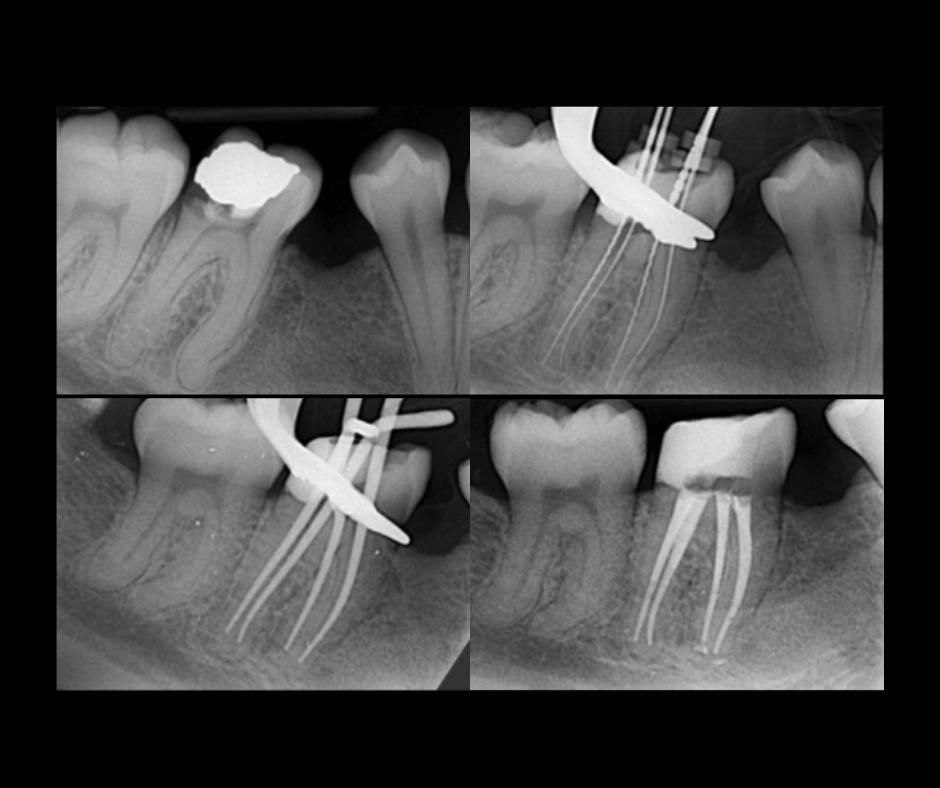

La endodoncia —conocida como “tratamiento de conducto”— es un procedimiento que permite salvar un diente afectado por infección, dolor o daño profundo.

2. ¿Cuánto dura el tratamiento?

Depende del diente y el caso, pero el procedimiento suele realizarse en una o pocas citas según la evaluación del especialista.

Te indicamos cuidados sencillos y realizamos controles para asegurarnos de que tu recuperación sea correcta.